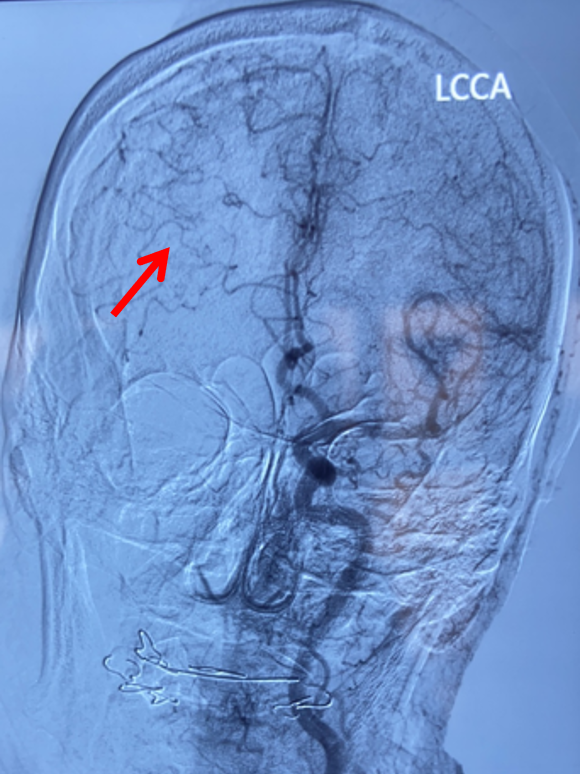

左侧椎动脉正位造影:可见双侧大脑后动脉显影良好,且右侧大脑后动脉通过软膜吻合向右侧大脑中动脉支配区域供血(箭头示)。